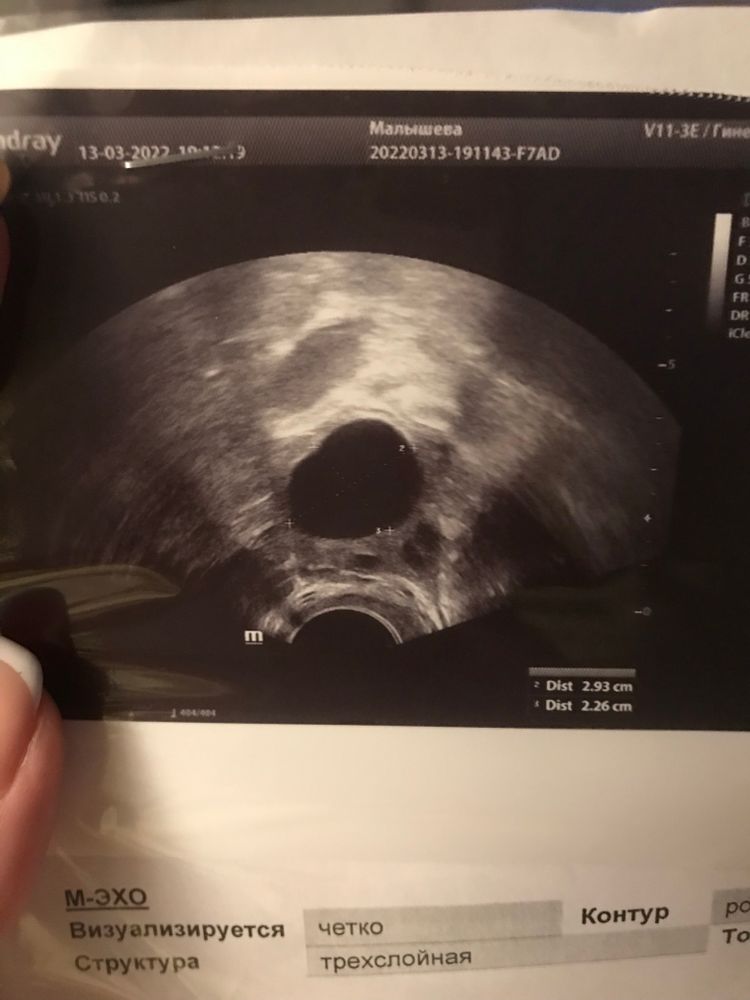

на 13дц эндометрий был 7,4 и на 15дц остался 7,4 это нормально или не верно измерили?

и фалликул был 16 стал 29,3 и Г написала персистенция фолликула, хотя у меня прям все ощущения овуляция были и тест был супер жирный на О